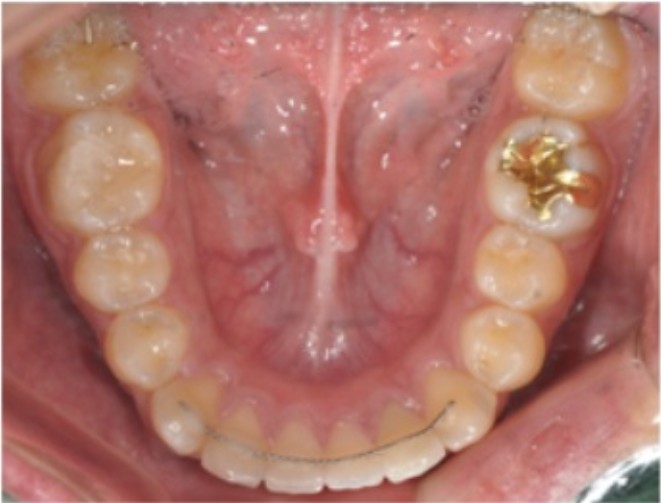

이제 다 끝났구나~! 교정 장치를 제거하고 나면 안도감이 듭니다. 하지만, 진짜 교정의 완성은 유지단계(retention)에서 결정된다는 걸 알고 계신가요? 실제로 많은 분들이 물어보십니다. “교정은 끝났는데, 왜 또 장치를 껴야 하죠?” 그때마다 저는 이렇게 말씀드립니다. “유지장치는 교정 치료의 마침표가 아니라, 느낌표입니다.” 교정이 끝나도 치아는 계속 움직입니다 교정이 끝난 바로 그 순간, 치아 주변 잇몸뼈(치조골)는 안정적이지 않습니다. 치아는 본래 위치로 돌아가려는 성질이 있어, 6개월 이내 재발률이 약 40%에 달할 정도로 움직임이 활발합니다. 그래서 ‘유지장치(retainer)’는 필수적입니다. 즉, 교정의 결과를 지키는 ‘안전벨트’ 역할이죠. 1. 유지장치는 어떤 종류가 있을까? 대부분 다음 두 유형 중 하나를 사용합니다. 가철식 유지장치 (Removable Retainer) 대표적으로 투명유지장치CR(clear retainer)와 WA(wrap around retainer)라 부르는 유지장치가 있습니다 세척이 쉽고 위생적으로 관리할 수 있지만, 착용을 소홀히 하면 치아가 바로 원위치로 돌아올 수 있습니다. 초기에는 하루 20시간 이상 착용하고, 이후 안정 단계에서는 취침 시에만 사용하는 경우가 많습니다.

고정식 유지장치(Fixed Retainer) 얇은 철사를 앞니 안쪽에 접착제로 부착한 형태입니다. 탈착이 불가능하고 눈에 띄지 않아 깔끔하지만, 양치 시 세균·치석 관리가 까다로운 점이 있습니다. 2. 유지장치 비용 (이미인교정치과 기준) 많은 환자분들이 궁금해하시는 부분이 바로 비용이죠. 환자분의 상태와 장치 재제작 유무에 따라 비용이 달라질 수 있습니다.